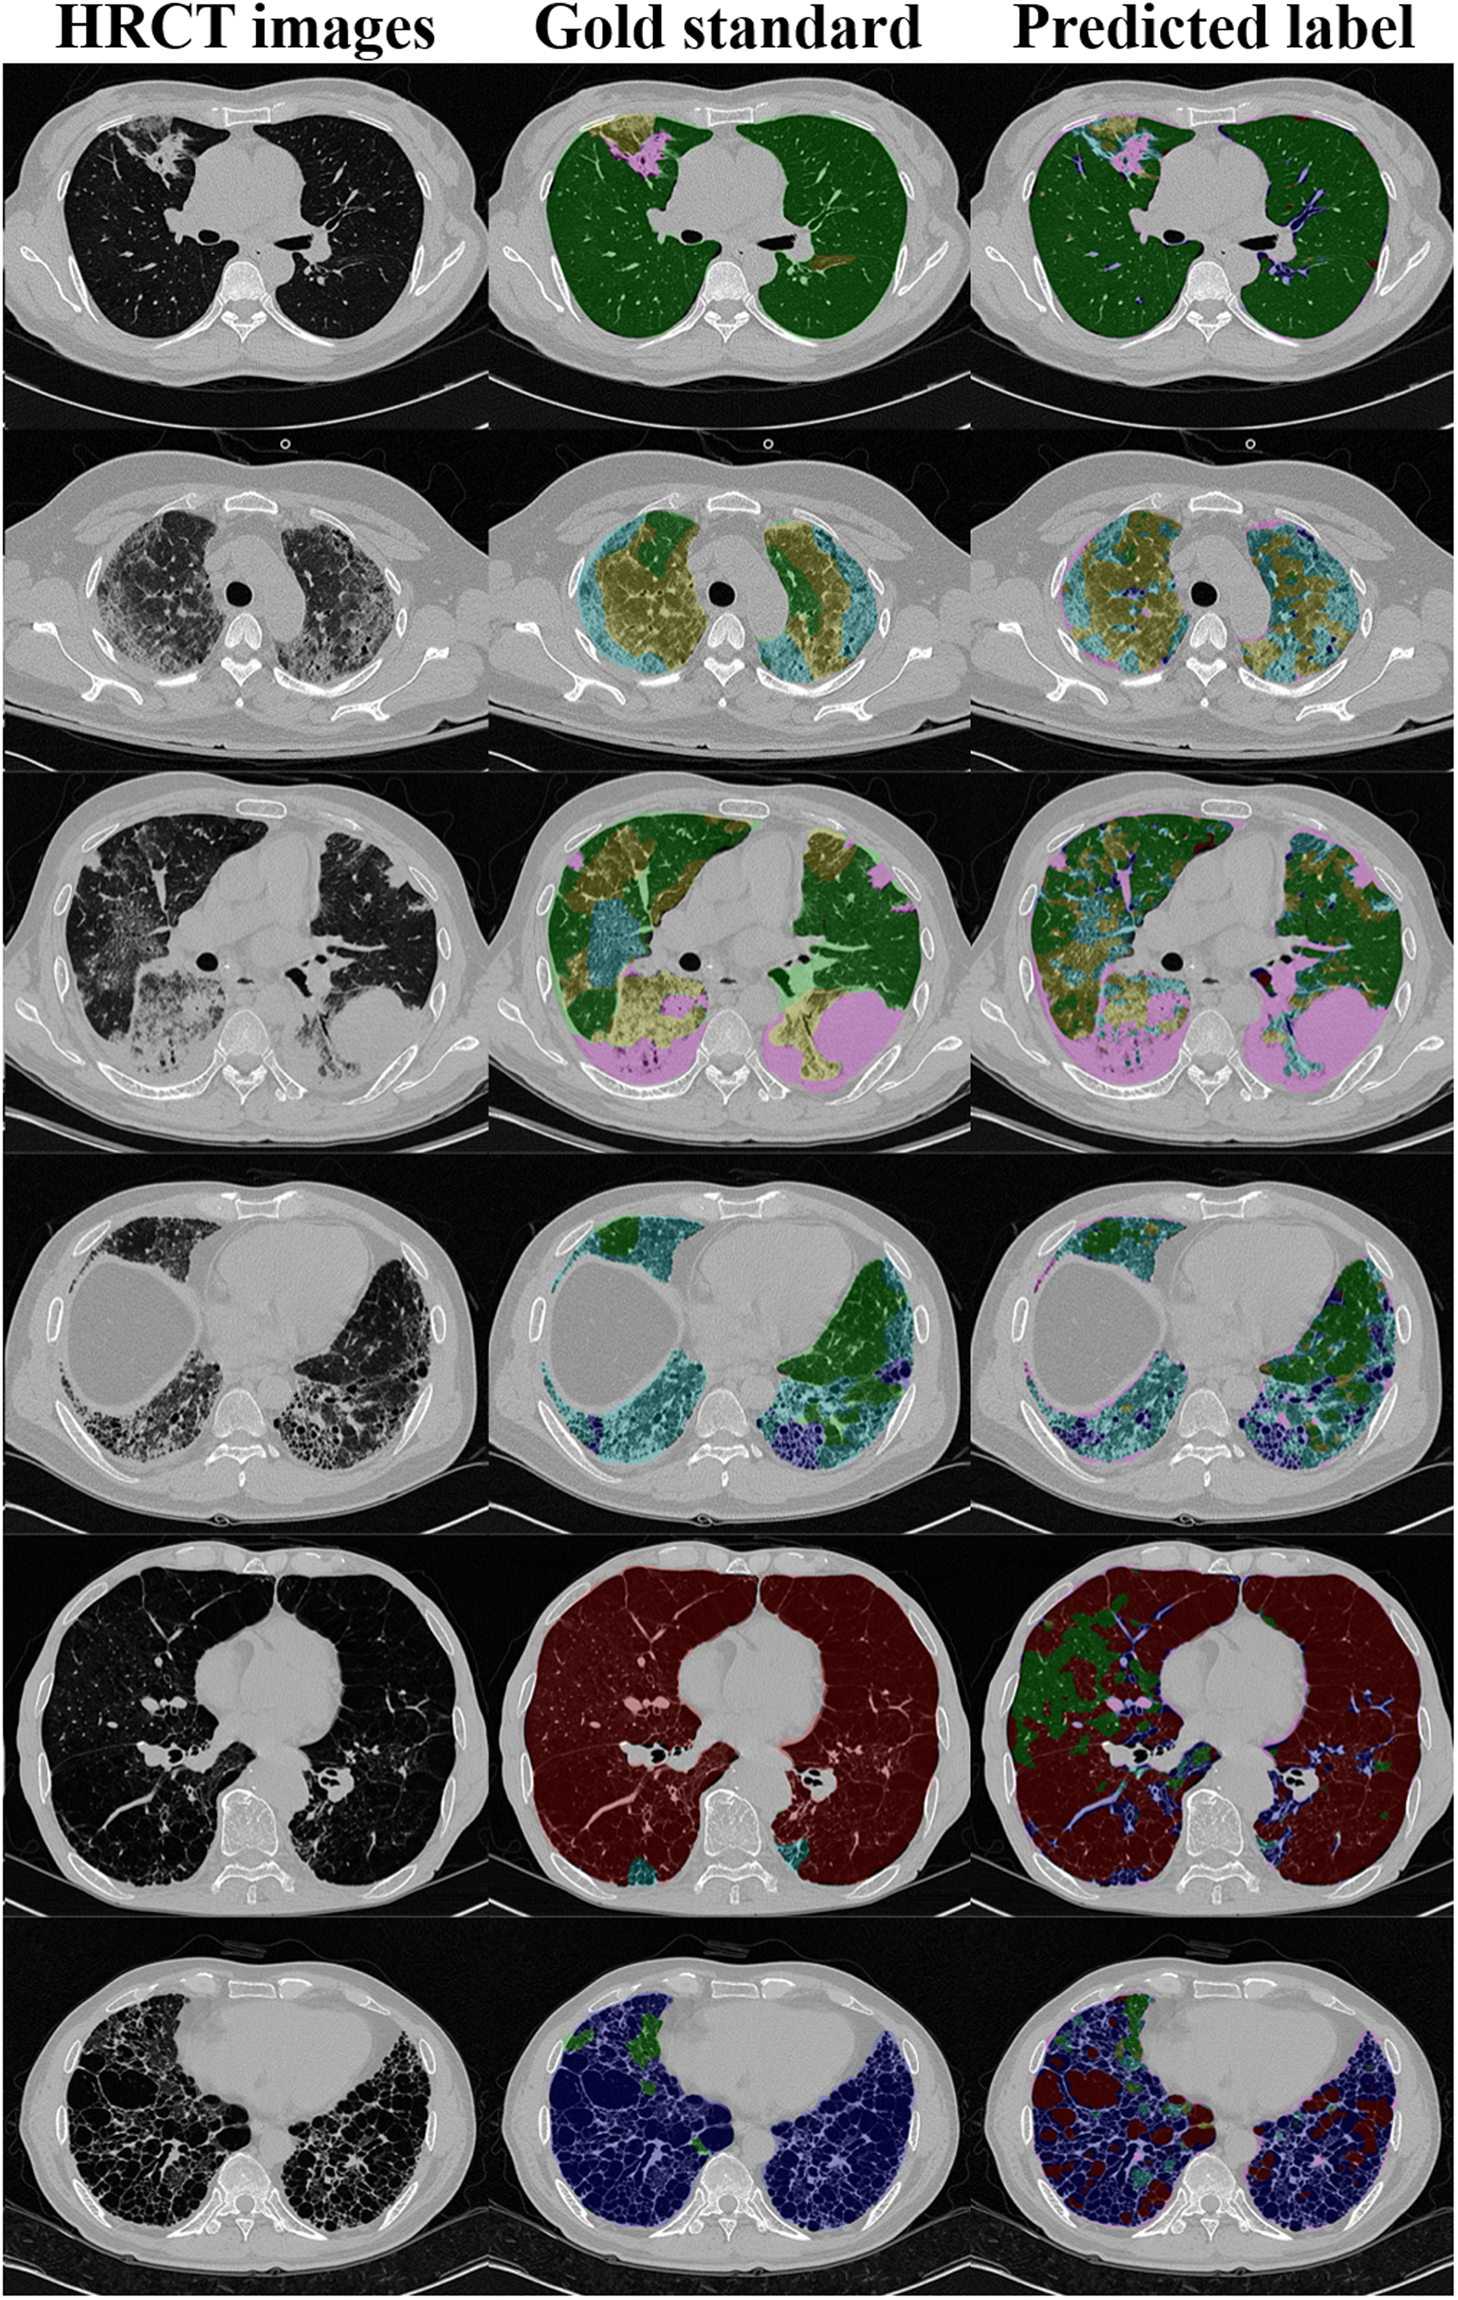

Figure 4

Examples of 2D HRCT images (left) with the corresponding gold-standard classifications of radiologist 2 (middle) and the CNN predicted labels (right). From top to bottom, the dominant patterns of DILD are normal (green), GGO (yellow), consolidation (pink), RO (cyan), emphysema (brown), and honeycombing (blue).